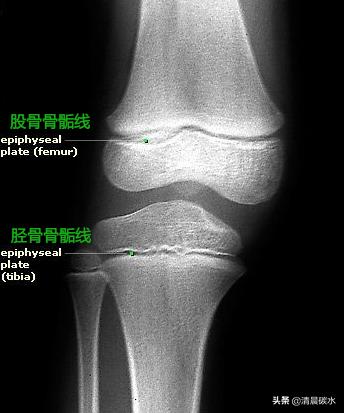

第三,骨骺板

骨骺板的活动与骨干的长长有着决定性的关系,也就是通常说的生长发育长个子。骨骼板的软骨细胞可以自己不断的增生(上图1),增生后,成骨细胞带着重建骨骼的原材料如蛋白质,钙和磷等营养物质(上图2,3),打造着强韧的骨骼,与此同时,也在不断的的骨化(上图3,4,钙质沉淀,硬度加强),这样就可以使骨骼长度不断增加。这个生化过程会一直持续到青春期后,大约23~25岁。这时,骨骺板也是被骨骼组织取代,变成了骺线。骺线的出现,意味着骨干就停止生长发育,人体增高的过程就不存在了。女性通常比男生提前2~3年完成骨化的过程。